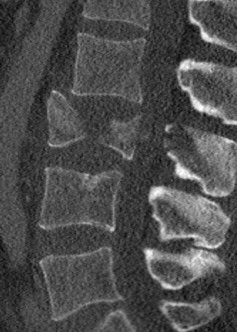

The fly-through doesn’t show the spinal injury very well, so here are some 2-D sections. The left panel is a section of my lumbar spine viewed from my left side; note the obviously smashed L3 vertebra. The middle panel is a top-view slide of L3, and the right panel is healthy L2 (the vertebra immediately above) for comparison.